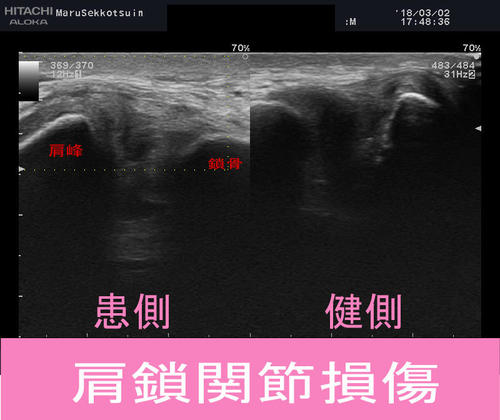

「肩鎖関節損傷(捻挫・脱臼)」

写真の通り、左肩(肩鎖関節)付近が大きく腫れ、

圧痛も強く、側方挙上も90度以上は困難。

今回の患者さまはエコーで確認しても、鎖骨のズレもなく「1度強損傷」。